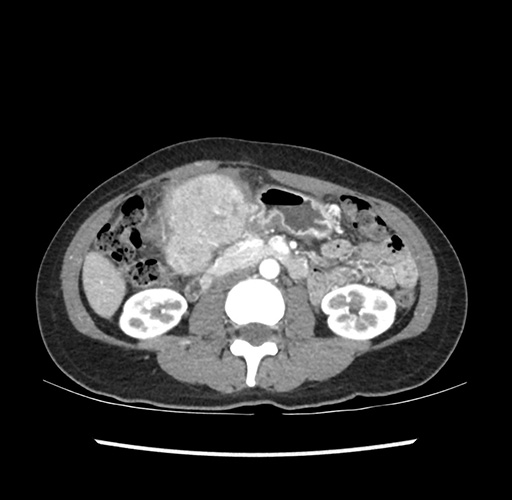

Imaging Analysis

Look through the patient's CT scan to identify any areas of concern for the necessary procedure.

Based on your CT findings, which issue(s) would give reason for "planned slowing down moment(s)" in this case?